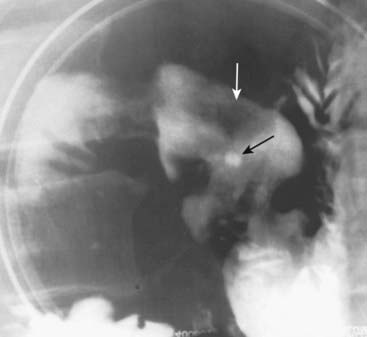

image Recognizing cavernous hemangiomas of the liver on CT and MRI:

Cavernous hemangiomas are usually hypodense lesions on unenhanced CT scans; they have a characteristic nodular enhancement from the periphery inward following injection of intravenous contrast and become isodense in the venous phase.

Contrast tends to be retained within the numerous vascular spaces of the lesion so that they characteristically appear denser than the rest of the liver on delayed (10 minute) scans (Fig. 18-33).

image

Figure 18-33 Cavernous hemangioma of the liver, triple-phase CT study.

(A) Cavernous hemangiomas (solid white arrow on all images) are usually hypodense lesions on unenhanced scans. They characteristically enhance from the periphery inward following injection of intravenous contrast during the arterial phase (B) and eventually become isodense. Contrast then tends to be retained within the numerous vascular spaces of the lesion so that it characteristically appears denser than the rest of the liver on delayed scans (C).